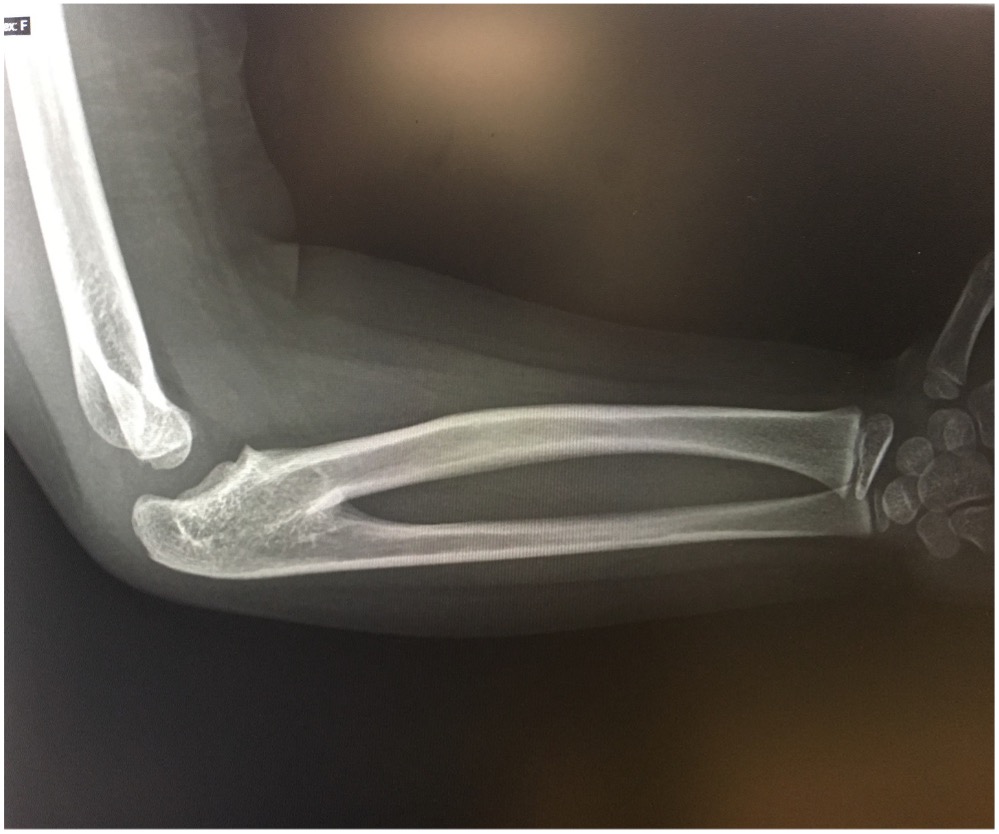

Some mild tenderness was noted upon deep palpation of the lateral elbow. The patient also had clinodactyly of the fifth phalange bilaterally. No other skeletal abnormalities were noted. A 3-view radiography scan of the elbow was conducted, results of which showed bilateral radioulnar synostosis (Figures 1-4). No wrist abnormalities were identified.

Figure 2. A radiology scan of the patient’s upper left extremity, medial view.

CRUS has been described based on radiological classifications, the anatomical location of synostosis, and how it influences functionality. The most common radiological classification of CRUS, described by Cleary and Omer, is based on the appearance of the synostosis and reduction of the radial head (Table).6,10 Type I occurs with no osseous synostosis but a reduced radial head. Type II occurs with bony synostosis. Type III occurs with osseous synostosis with a hypoplastic and posteriorly dislocated radial head. Type IV occurs with short osseous synostosis with an anteriorly dislocated radial head. The radiological findings in our patient depicts a type II congenital radioulnar synostosis (Figure 1). Another description was explained by Wilkie, for which type I shows a connection between the radius and ulna occurs at the medullary canal; with type II, the fusion occurs distal to the proximal radial epiphysis and the radial head is dislocated anteriorly or posteriorly.4 A third description, which pertains to just the proximal radioulnar synostosis has also been portrayed.11 In type I, there is an absence of the radial head followed by complete radioulnar synostosis. In type II, the proximal part of the radial head is present but often deformed, and fusion occurs at the neck of the ulna. In type III, the head of the radius is always deformed and subluxed with synostosis occurring at the proximal area of the interosseous bones.